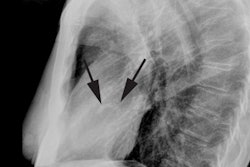

X-ray:

The chest radiograph has a low sensitivity for detecting coronary artery calcification. The best site to detect coronary artery calcification on the PA CXR is along the mid left heart border (the left main, and proximal portions of the left anterior descending and left circumflex arteries lie in this location). CAC appears as thin, parallel white lines on the chest radiograph. The accuracy of CXR for detecting coronary calcifications is only 42% [4]. Plain film evidence of coronary artery calcification in symptomatic patients under the age of 65y, is almost always (nearly 100% incidence) associated with significant coronary artery disease. About 30% of asymptomatic patients will also have significant narrowing.